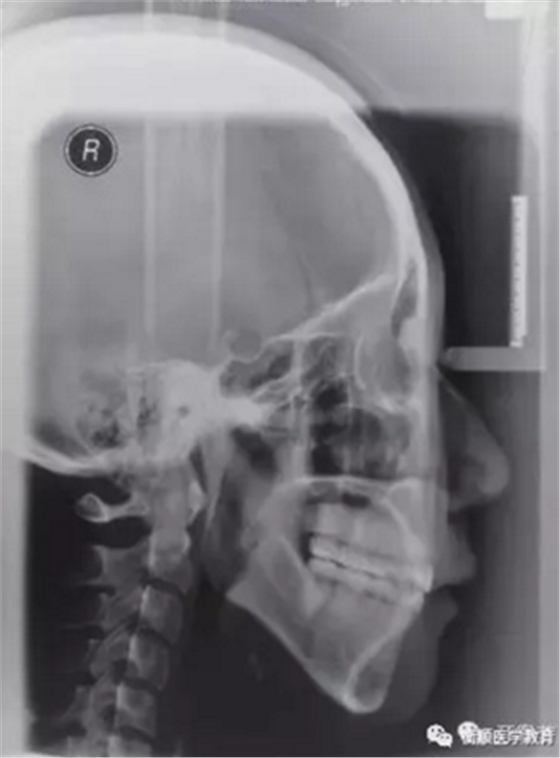

图6 治疗后头颅侧位片